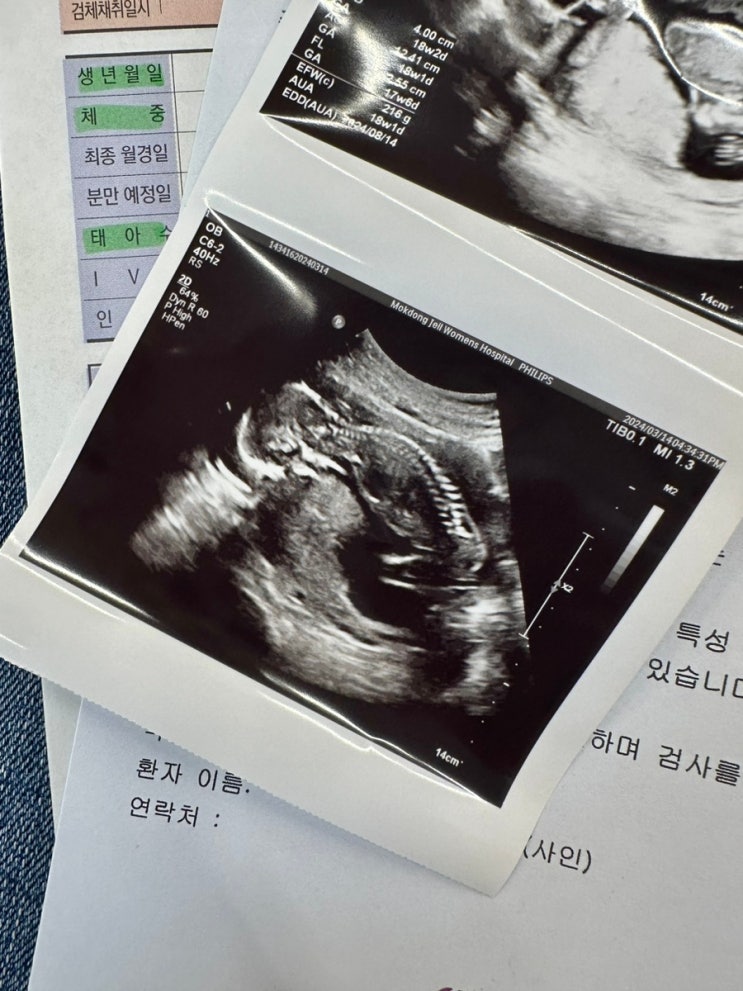

임신 21주 태동 심함 ㅎㅎ 22주 정밀초음파

임신 21주 드디어 시작된 태동 장난 아님 임신 22주 정밀 초음파 검사 및 몸무게 증가 임신 21주 차 24.04....